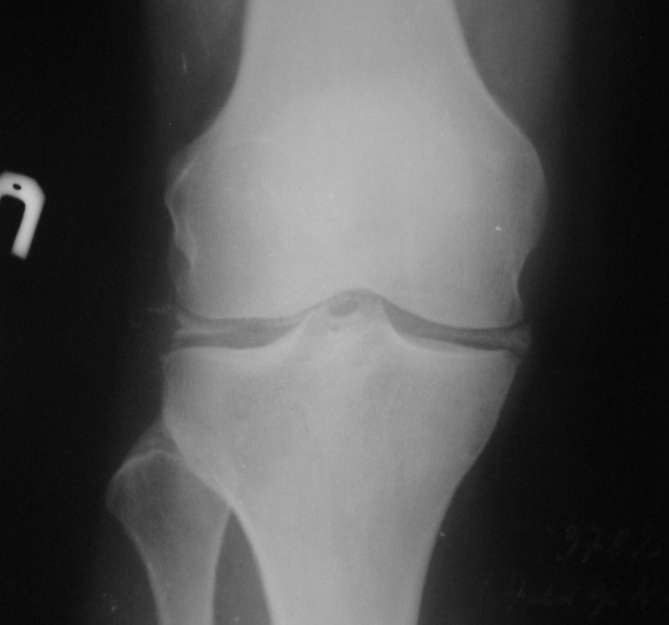

Здравствуйте, коллеги.На поликлиническом приеме ко мне обратилась девушка 35 лет с готовым снимком, жалобами на боли и отек правого коленного и голеностопного суставов. Похоже на кальциноз менисков.

Поразительно, но процесс кальцификации затронул только мениски - капсула интактна, периартикулярных теней нет. Г/стопный сустав - б/о. Поставил DS: Кальциноз менисков правого коленного сустава. Остеоартроз I степени по Kellgren. Реактивный синовит. Болевой синдром II степени. Нарушение функции I степени.

Да кальциноз имеет место. У "девушки" 35 лет наверно когда-то имели место травмы.На снимке видны признаки лигаментоза.Артроскопия-да.При финансовых проблемах можно- артротомия,менискэктомия,ревизия межмыщелкового возвышения,дебриджмент,зачистка очагов хондромаляции.

Уважаемый Никита! Встречал подобных больных, но патология проявляется в более зрелом возрасте. Оперировали артроскопически. Находили мениски покрытые мелкими круглыми крупинками белого цвета размером 0,1- 0,3 мм (вероятно пирофосфат кальция), местами сливающимися в сплошной крупитчатый ковер; хрящевой покров мыщелков тусклый, слоится, в трещинах и эрозиях; на внутреннем мыщелке бедра и большеберцовой кости имеются участки оголенной кости размером 1 х 1 см, и 0,5 х 0,5 см.; мениски тусклые, края бахромчато разволокнены, растресканы - это часть протокола операции. Это, по-моему,болезнь отложения кристаллов кальция пирофосфата дигидрата (БКПД).Иное название - псевдоподагра. Протекает на фоне синовиита, возможна киста Бейкера и повреждение "инкрустированных" менисков. Дребует диф.диагностики с ДОА, возможно сочетание этих двух болезней. Относится к микрокристалическим артропатиям.